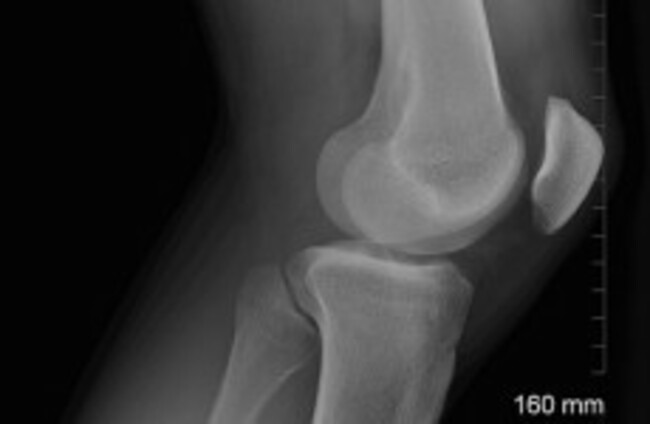

Further study needed on effectiveness of knee implants - report

MEDICAL RESEARCHERS HAVE issued a warning about the lack of evidence regarding the safety or effectiveness of different types of knee replacement implants currently available, Irish Medical News reports.

In a report published in the Lancet, UK researchers have called for further research into the long-term safety and comparison of different knee implants.